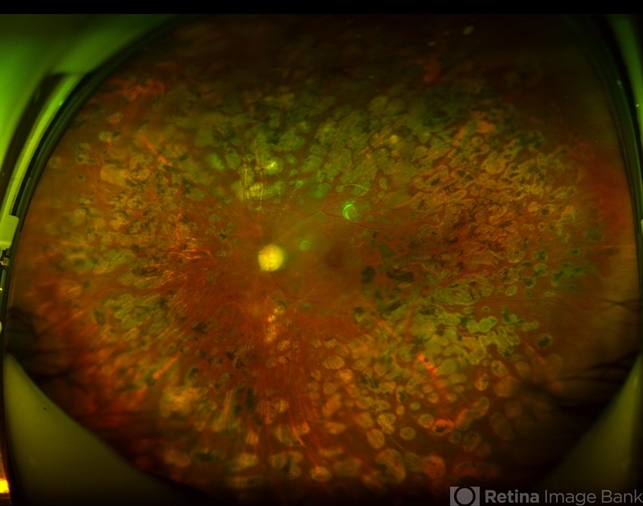

- diabetes, laser photocoagulation

- Extensive pan-retinal photocoagulation in a Mexican patient that was required to inactivate the disease.